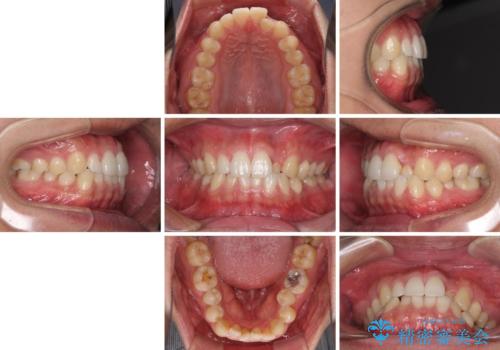

- 前歯のデコボコとクロスバイトを治したいとのことで来院された患者様です。

上下顎ともに歯列全体の側方拡大を行い、下顎前歯はIPR(歯と歯の間を削る)によってデコボコとクロスバイトが解消するように設計し、インビザラインにより治療を行うこととしました。

2年弱で終了する予定でしたが、途中来院されなかった時期があり、その後舌側転位している前歯を動かせるところまで動かしたいとのことで4年ほど治療を継続されました。